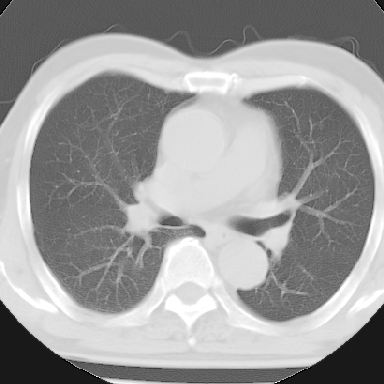

纵隔窗呢?慢支炎肺气肿;余未见明显渗出及占位!

慢性支气管炎、肺气肿。

慢性支气管炎并肺气肿

不支持慢性支气管炎,另外慢性支气管炎的诊断需结合临床病史才能诊断。

就以上的片子,如果没有明确的病史,说未见明显异常也不过份吧

这份病例诊断慢支并气肿可能属过诊,首先慢支的临床诊断标准是严格的,应该弄清楚,其次ct表现是否符合该病表现,本例老年人ct肺窗表现应属正常,不要跟着临床跑。